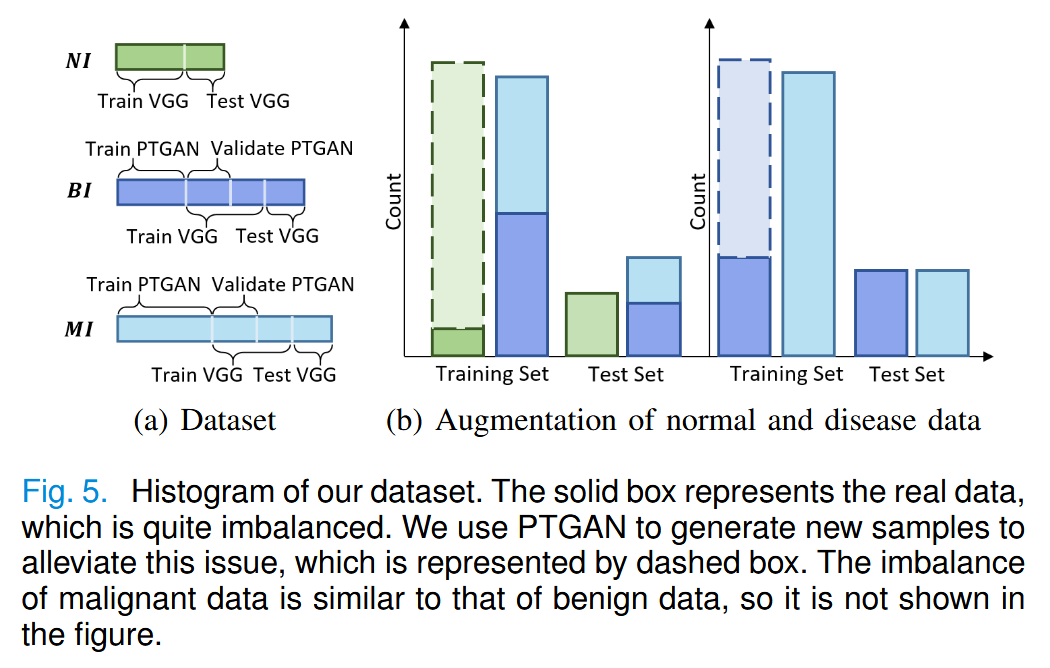

在图6中,我们展示了真实疾病图像(包括良性和恶性)、由 PTGAN 生成的图像、PTGAN 无 PTM、PTGAN 无 RM、PTGAN 无 PTM&RM的生成图像。

PTM 能够引导网络生成更有意义的结构和纹理。没有 PTM 的模型生成的结构和纹理更加混乱。

RM 使生成图像的细节更加真实,包括超声图像特有的斑点噪声。

我们使用相同的训练策略与最新的图像修复方法[38]、[39]进行比较,如图6的最后两行所示。显然,我们的方法在病变重建方面具有更优越的效果。

对于掩膜与动脉低回声区域相连的情况(第一列和第四列),现有方法无法重建被破坏的血管壁。我们的方法在有效恢复正常组织纹理的基础上,能够重建被掩膜的血管壁。